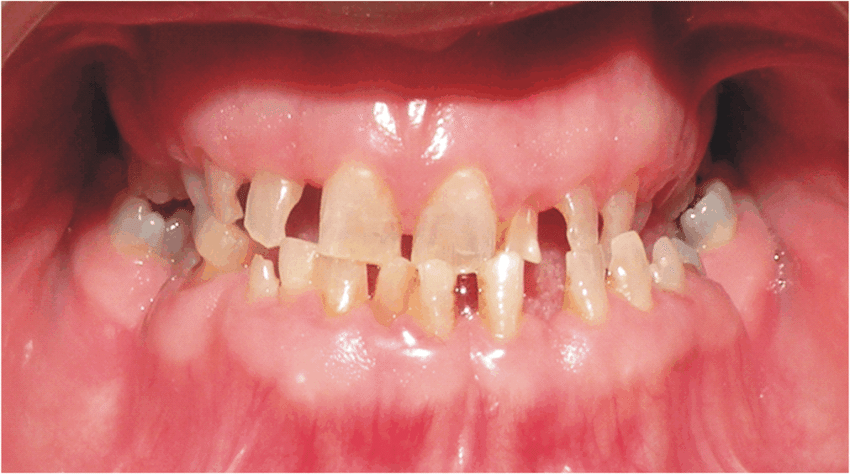

- 1. Hypoplastic:

- Areas of tooth enamel fail to form normal contour

- Enamel is normal hardness but thin

- Sharp needle like cusps/ pitting/ vertical grooving & wrinkling

- Yellow + gross attrition with time